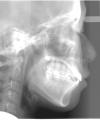

日本矯正歯科学会専門医課題症例(その他の症例2)

カテゴリー:埋伏歯牽引症例(代替症例)

埋伏歯を矯正歯科的に牽引することで、正常咬合を確立できた症例。

埋伏歯は、歯の萌出する隙間の不足、萌出方向の不良、萌出力不足、腫瘍または囊胞などの障害物により萌出路が塞がれている場合などに生じる病気である。いったん萌出が妨げられると、原因が除去されても自然萌出に至らないことが多く、そのままでは埋伏歯が使えないだけでなく、正常咬合が確立できない事態となる。

最良の解決策は、口腔外科的に開窓後、矯正歯科的に牽引し咬合に参加させることである。単に萌出させたと言うだけでなく、牽引後マルチブラケット装置を使用し、正常咬合を確立したケースの提示が求められている。